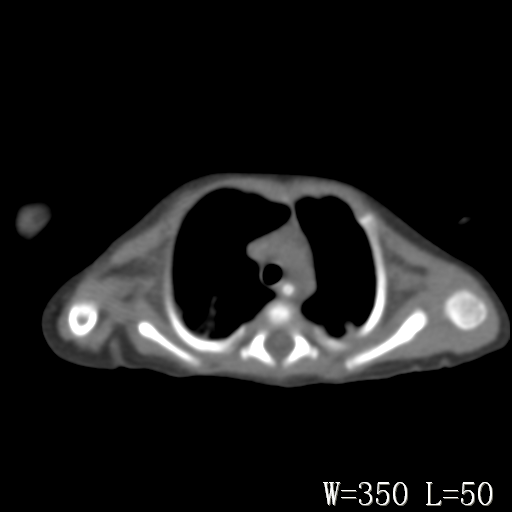

以下是引用改行者在2010-7-8 22:13:00的发言:[br]两肺野透光度降低伴细颗粒状影,两肺下叶见实变影,其内见支气管充气征。 多考虑新生儿肺透明膜病。